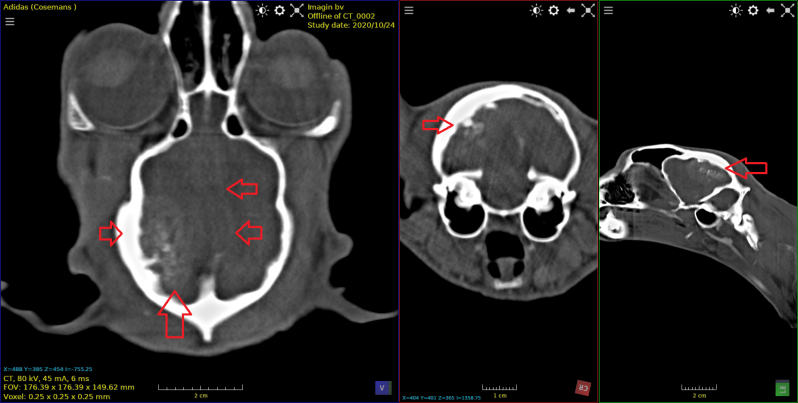

Keeshond van 5 jaar met een adenocarcinoom in de neus

beeld na toediening van contrast . Captatie van contrast in tumor